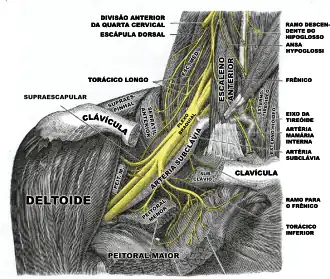

O nervo frênico desce obliquamente com a veia jugular interna através do escaleno anterior, para a camada pré-vertebral da fáscia cervical profunda e as artérias cervical transversa e supraescapular. À esquerda, o nervo frênico cruza para a primeira parte da artéria subclávia. À direita, encontra-se na parte anterior do músculo escaleno e cruza para a segunda parte da artéria subclávia. Em ambos os lados, o nervo frênico segue posterior a veia subclávia conforme ela entra no tórax, onde ela segue anterior para a raiz do pulmão e entre o pericárdio fibroso e da face mediastinal da pleura parietal.[1]

Encontrado no meio do mediastino, ambos os nervos frênicos seguem a partir dos nervos C3, C4 e C5 ao longo do músculo escaleno anterior para a bainha carotídea.

A contribuição do 5º nervo cervical pode vir a partir de um nervo frênico acessório. O nervo frênico perto da sua origem, é um ramo de comunicação para raiz C5 do plexo braquial. O nervo frênico, no nível da raiz do pescoço, pouco antes de entrar no tórax, fica a frente da veia subclávia. Normalmente, é colocado de forma posterior, entre a veia e a artéria subclávia.[3]

O direito do plexo braquial com seus ramos curtos, visto de frente.

O direito do plexo braquial com seus ramos curtos, visto de frente.